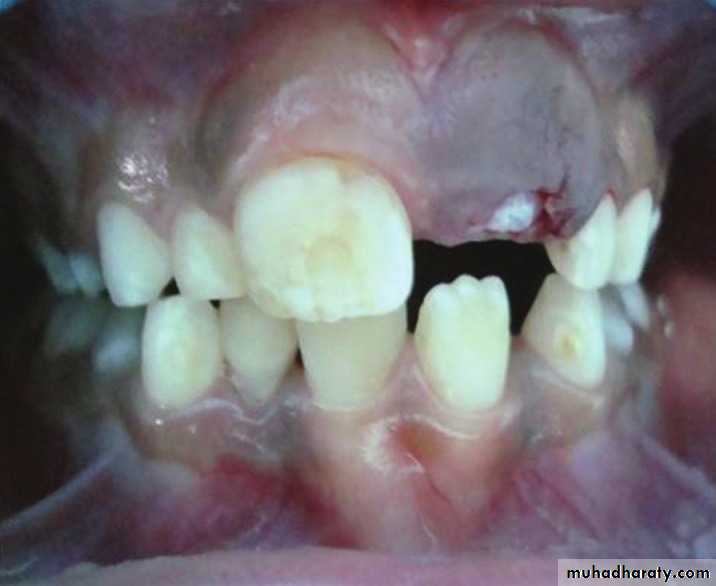

*A 13 year old boy presents with a recurrent friable granular lesion of the anterior maxilla. This is a recurrent lesion after excision.

Differential Diagnosis:

• Pyogenic Granuloma• Peripheral Odontogenic (Ossifying) Fibroma

• Peripheral Giant Cell Granuloma

• Squamous Cell Carcinoma other soft tissue malignancies